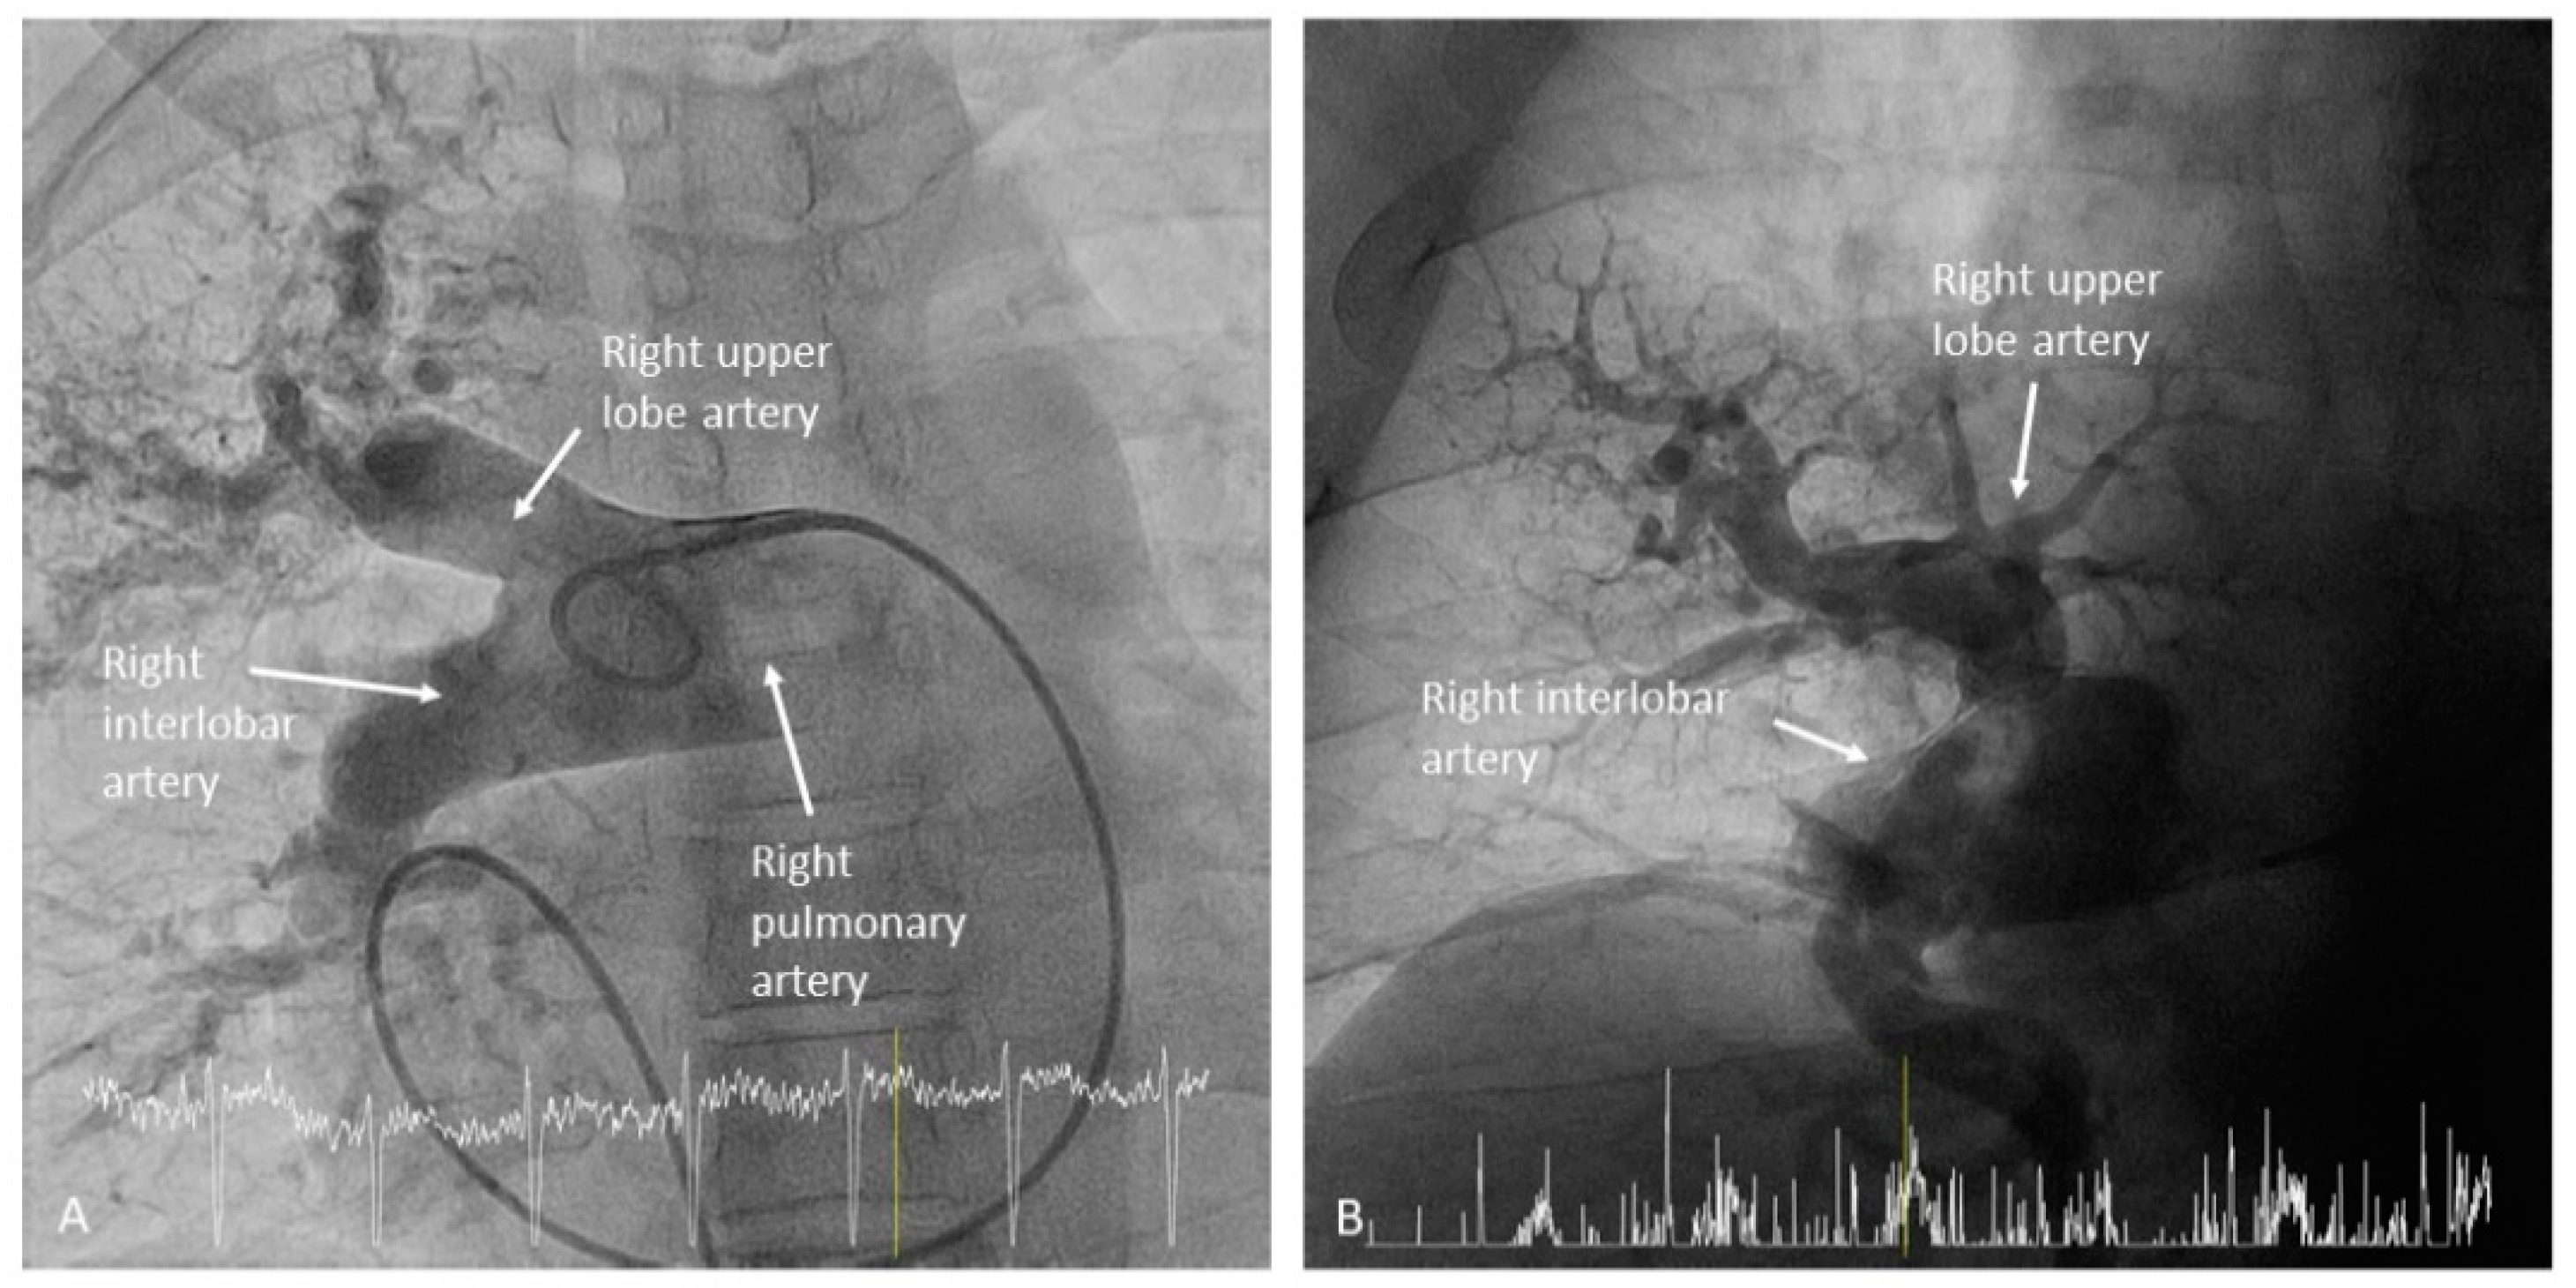

- Right upper lobe. The right upper lobar artery arises about 10 cm from the bifurcation. It is cannulated in the AP view with the tip of the MP-A2 facing upwards. The apico-posterior segmental artery (A1/2) is canalized just by advancing the MP distally once in the right upper lobe artery. The AP and lateral views display the apical (A1) and posterior branches (A2) (Figure 28). The anterior segmental artery (A3) is canalized in the lateral view, rotating the MP counterclockwise from its position in the apico-posterior artery (A1/2). With this maneuver, the tip of the catheter moves downwards, facing the sternum and engaging the anterior segmental artery (A3) (Figure 29). This branch should be filmed in lateral and cranial AP/cranial LAO view.